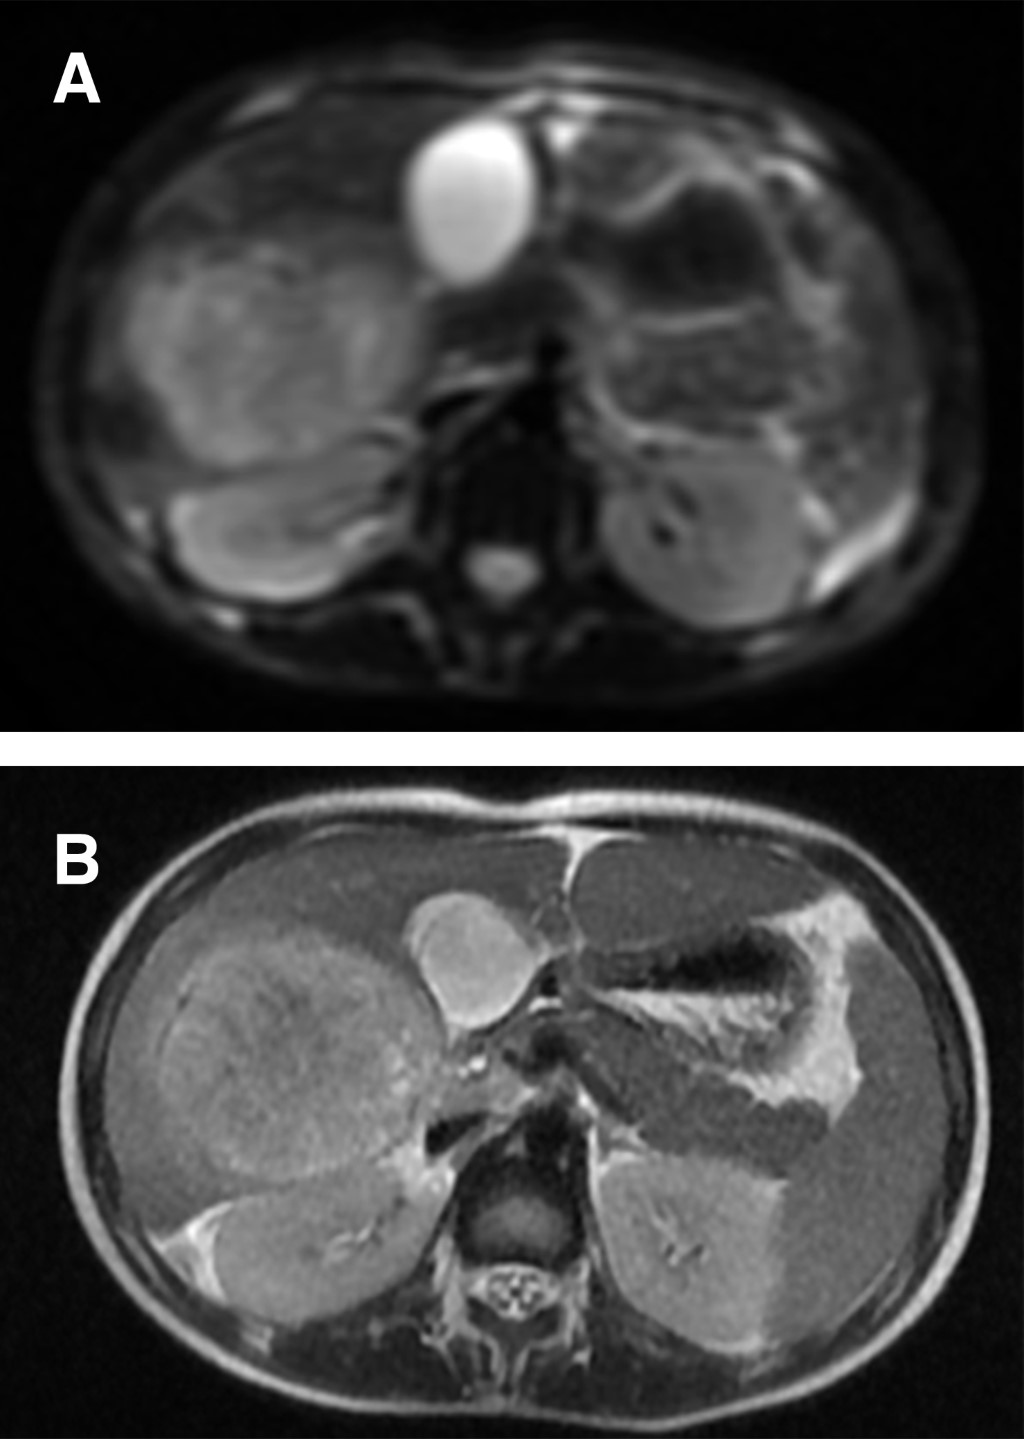

En el hospital de origen se solicitó una analítica sanguínea donde destaca leucocitosis de 24,330 cél./μL, neutrofilia de 20,800/μL, proteína C reactiva (PCR) de 247.3 mg/L, procalcitonina (PCT) de 1.30 μg/L y alteración de la coagulación con tiempo de protrombina alargado de 18.6 s, índice internacional normalizado (INR) de 1.68 y fibrinógeno superior a 500 mg/dL. Ante sospecha de apendicitis aguda se solicitó ecografía abdominal (Figura 1), se evidenció una lesión focal heterogénea y con flujo Doppler en lóbulo hepático derecho se planteó el diagnóstico diferencial entre absceso hepático y hepatoblastoma.

La ecografía es el estudio de imagen inicial de elección, con una alta sensibilidad (80-95%); además, permite descartar enfermedad biliar asociada. La tomografía axial computarizada es la prueba de imagen de mayor sensibilidad (97-100%). Sin embargo, últimamente se está postulando la resonancia magnética como prueba de elección, ya que permite realizar el diagnóstico diferencial entre distintos tipos de lesiones hepáticas, descartar la presencia de lesiones en otras localizaciones y definir anatómicamente la lesión con exactitud. Característicamente, los abscesos hepáticos son hipointensos en T1, hiperintensos en T2, captan gadolinio de manera perilesional en T1 y restringen a la difusión.17